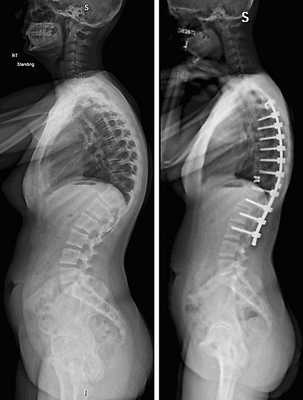

- дегенеративные патологии, сопровождающиеся неврологическим дефицитом, например, межпозвоночные поясничные грыжи; и кифоз;

- несостоявшийся артродез;

- последствия неудачно выполненных вмешательств и др.

Коррекция кифоза грудного отдела.

Абсолютными противопоказаниями являются локальная деградация костной ткани (остеопения и остеопороз), местный инфекционно-воспалительный процесс, непереносимость металлов.